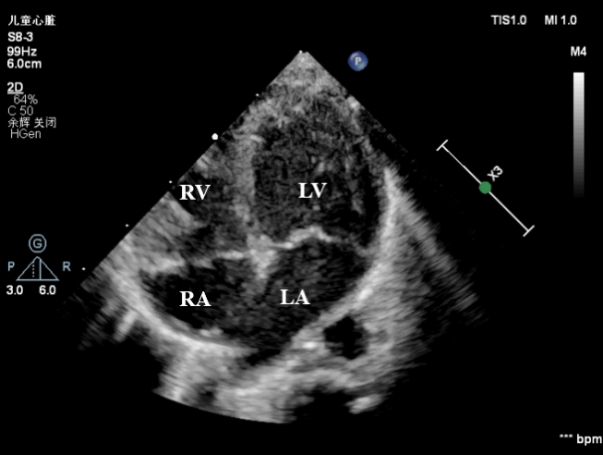

7月19日上午11点40分,孕妇通过剖腹产生下一名体重不到6斤的男婴,出生后宝宝由于缺氧全身呈蓝紫色,呼吸微弱,身体各项指标非常差。心血管超声医学科王斌主任立即床旁急诊超声检查,心脏超声提示:内脏、心房正位,左位心,心室右袢,房室连接一致,心室与大动脉连接不一致,室间隔完整的完全性大动脉转位(S.D.D),细小动脉导管未闭(双向分流),左、右心室发育尚可(见下图)。

房室连接一致,室间隔连续完整(LA:左房;LV:左室;RA:右房;RV:右室)